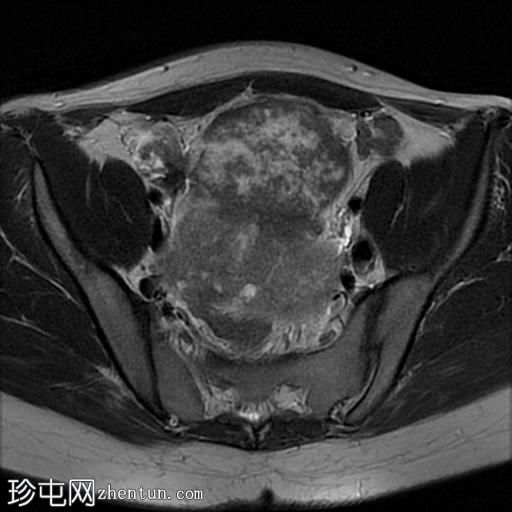

盆腔内可见多个边界清晰的肿块:

其中一个位于子宫上方,T2加权像呈中等信号,中心区域呈高信号,增强T1脂肪抑制像未见强化。右侧卵巢增大,增厚的血管蒂扭曲,未见强化,轴位和矢状位T2加权像均显示清晰。

另一个位于子宫后窝,T2加权像呈中等信号,增强扫描显示明显强化。

轻度腹腔积液

2个月前进行的MRI检查显示双侧卵巢肿块均有强化,右侧卵巢肿块未见扭转。

Krukenberg瘤患者单侧卵巢扭转的MRI特征。

Krukenberg瘤引起的卵巢扭转在文献中鲜有报道。